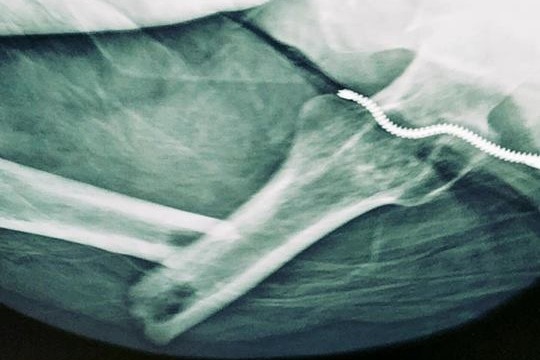

On Friday Oct 19th, Jenn suffered a traumatic fall that resulted in breaking the largest bone in the body, her femur. This injury subsequently resulted in surgery to have a rod & screws placed through the bone from her hip to her knee. This injury has caused Jenn to be out of work for 6+ months, with no expected date of return as the bone has a delay in healing. She has been referred to a bone trauma specialist, & possibly looking at another surgery. She has received the maximum disability allowed in NYS, & with 4 kids to provide for, it is causing a huge financial strain on her family. Any help would be greatly appreciated by Jenn & her children to alleviate some of the financial burden.